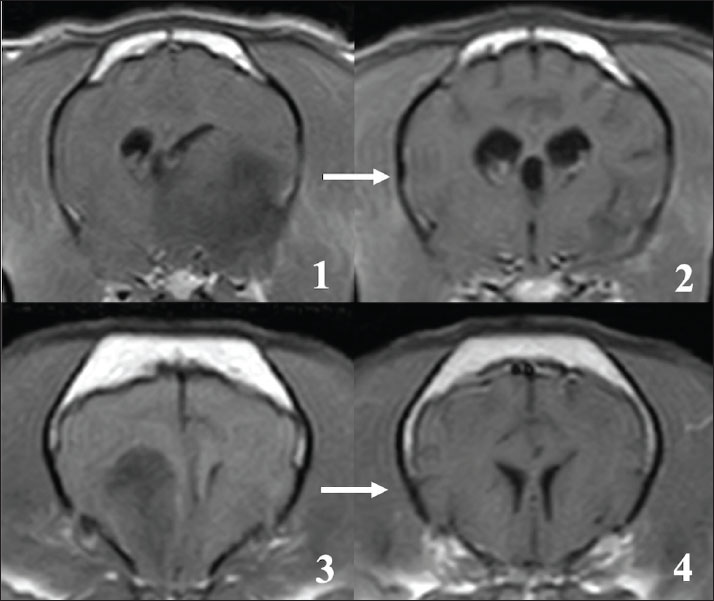

Brain tumors in all 15 cases were present in the cerebrum and were suspected to be tumors derived from glial cells (Fig. 1). Among the 15 cases, 14 cases had a single tumor site, and one case had 2 tumor sites in the cerebrum on MRI. Furthermore, 11 of the 15 cases appeared to be in contact with the lateral ventricles, and in 3 cases, the tumor tissues seemed to invade into the lateral ventricles on MRI. Although the signal intensity on MRI of these glial tumors varied, most cases showed low to iso-signal intensity on T1-weighted images and iso- to high-signal intensity on T2-weighted images. The enhancing effect of the contrast medium also varied among the cases; one case showed a clear ring-enhancing effect, 2 cases showed homogenous enhancement (one case with a ring-shaped periphery), and 7 cases showed heterogenous enhancement (three cases with a ring-shaped periphery). The remaining 5 cases showed almost no enhancement. Cerebellar herniation, possibly induced by the intracranial tumor, was observed in two cases. Additional CT evaluations of the thoracic and abdominal cavities at the first visit showed no distant metastatic lesions and other abnormal findings in any of the patients.

Fig. 1. Typical MRI findings of the presumed glial tumors observed in this study. In many cases, brain tumors showed low signal intensity on T1-weighted images (1) and high signal intensity on T2-weighted images (2). Various enhancing effects were observed in the contrast examination, but most of them showed relatively weak enhancement (3). Some tumor tissues that clearly protruded into the ventricles were also observed (4, asterisk).